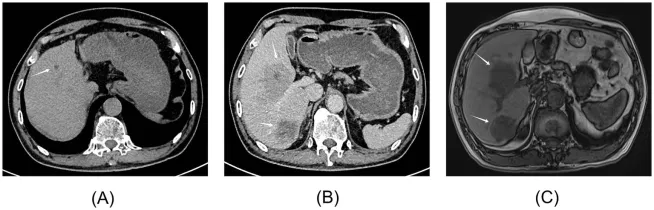

图1. 病例1的影像学表现

(A)2023年9月腹部平扫及增强CT显示,肝右叶可见一低密度灶,大小约2.3×2.1×1.4 cm,当时拟诊为“不典型肝血管瘤”。(B)2024年9月上腹部增强CT提示,肝S5、S6段各见一边界相对清晰的类圆形低密度影,较大者约8.8×8.2 cm。增强后动脉期病灶边缘呈明显强化,静脉期及延迟期持续强化。(C)2024年9月上腹部MRI(包括平扫、增强、弥散加权成像及磁共振胰胆管成像)显示,肝S5、S6段占位性病变大小分别约为10.0×8.0 cm及4.4×3.8 cm,肝门区可见淋巴结肿大。

临床确诊与诊断依据:2024年9月,患者因上腹部钝痛来诊。查体见肝区叩击痛。实验室检查显示,血清AKR1B10显著升高至6239.29 pg/mL(参考范围:0~369.30 pg/mL),而AFP与CEA仍为阴性。天冬氨酸转氨酶升高(75.90 U/L),AST/ALT比值达3.47,尿胆原为1.0 μmol/L。腹部超声提示肝内两处高回声肿块,大小分别为9.0×8.0 cm与4.2×3.7 cm,边界清晰,内部回声不均,可见血流信号。上腹部增强CT显示肝S5、S6段见类圆形低密度影,边界较清,较大者约8.8×8.2 cm(图1B),增强后呈动脉期边缘强化、静脉期及延迟期持续强化的“快进慢出”表现。MRI进一步明确肝S5、S6段占位,大小分别约为10.0×8.0 cm与4.4×3.8 cm(图1C),并提示肝门区淋巴结肿大。

该患者被临床诊断为原发性HCC(累及门静脉右支)。根据欧洲肝脏研究学会(EASL)最新临床实践指南与LI-RADS(2018版)分类标准,病灶符合非环状动脉期高强化、无周边廓清、伴有包膜强化的影像学特征,归类为LR-5(明确的HCC),故未行侵入性病理活检。图2汇总了本病例的关键就诊时间线与诊断过程。